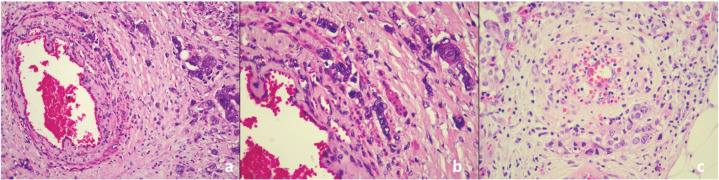

Methods: A total of 150 patients with breast cancer diagnosed between July 2020 and January 2022 were included. Clinicopathological data were retrieved from the hospital records. The presence of PVI was evaluated on hematoxylin&eosin stained slides, and the association between PVI and clinicopathological parameters was statistically analyzed. A p-value of <0.05 was regarded as statistically significant.

Results: All patients were female. The mean age was 54.0±13.6 years (range 26-97 years). PVI was significantly more common in patients with ≥2.5 cm tumors and the absence of PVI showed a significant correlation with a lower histologic grade (p=0.004 and p=0.040, respectively). Lymphovascular invasion (LVI) and perineural invasion (PNI) were also significantly more frequent in tumors with PVI (p=0.001 and 0.02, respectively). There was a statistically significant association between the absence of both PVI and extranodal extension (ENE) (p=0.035).